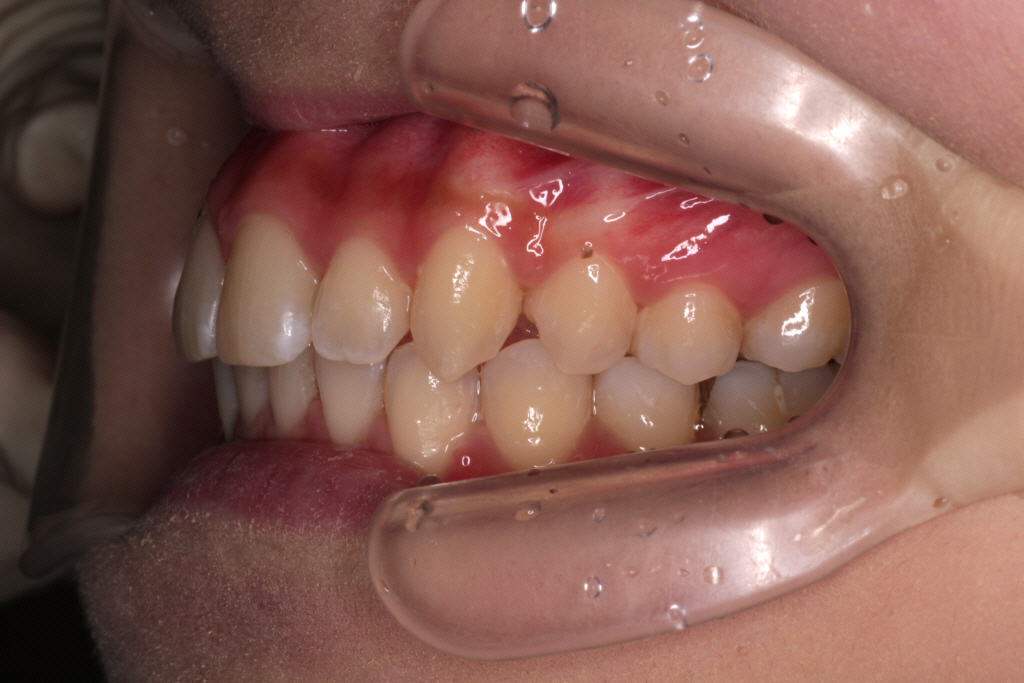

↓お口の中の状態です。

初診時からの変化と治すべきところは

⑴咬み合わせは下の歯が上の歯に隠れていましたが、見えるようになりました。

⑵右下の2番目の歯が歯列の中に納まってきましたが、まだ少しずれています。

⑶右上の2番目の歯は下の歯より前に出ましたが、咬み合わせが浅いです。

ここで新たな問題点が見つかりました。

⑷正中がずれているので、合わせるためにゴムかけをします。